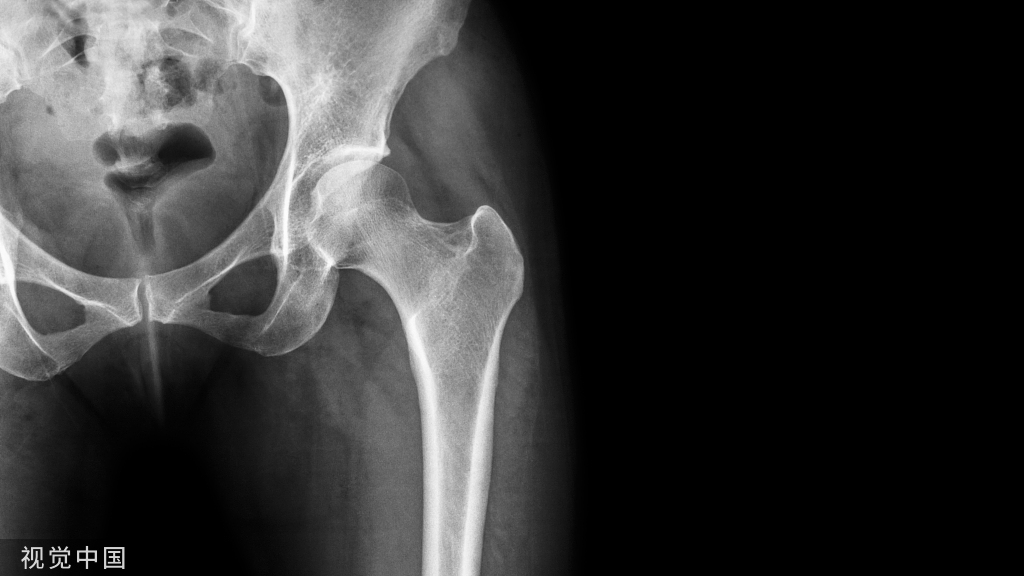

重建术后X片